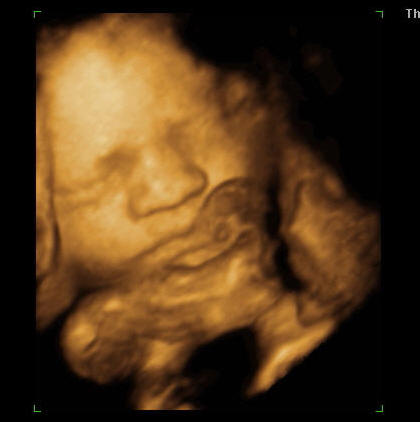

Addig is 2kép az állatkertből:

a 3d-s szemüvegben